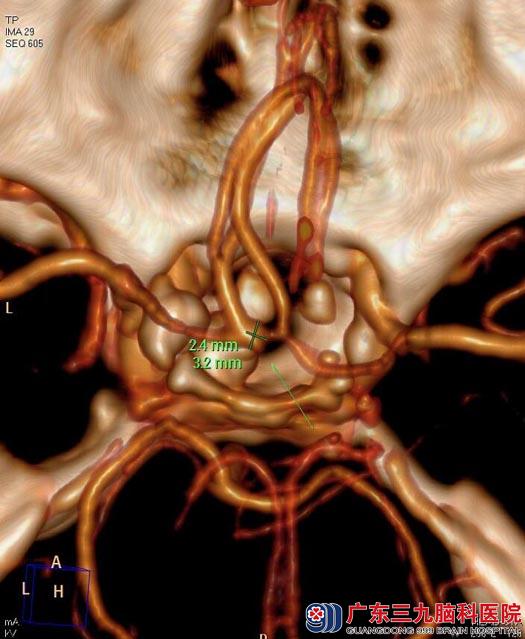

住院在广东三九脑科医院综合神经外科。头颅MR检查结果:鞍内及鞍上示一不规则异常信号影,范围约为2.4cm×2.7cm×3.1cm,考虑颅咽管瘤可能;头颅CTA检查显示:鞍区(鞍上为主)占位性病变,前交通动脉偏左侧囊状突起影,考虑动脉瘤(小型);内分泌检查报告:垂体前叶功能低下。予左甲状腺素口服治疗,两周后患者甲功基本正常。

▲术前CTA